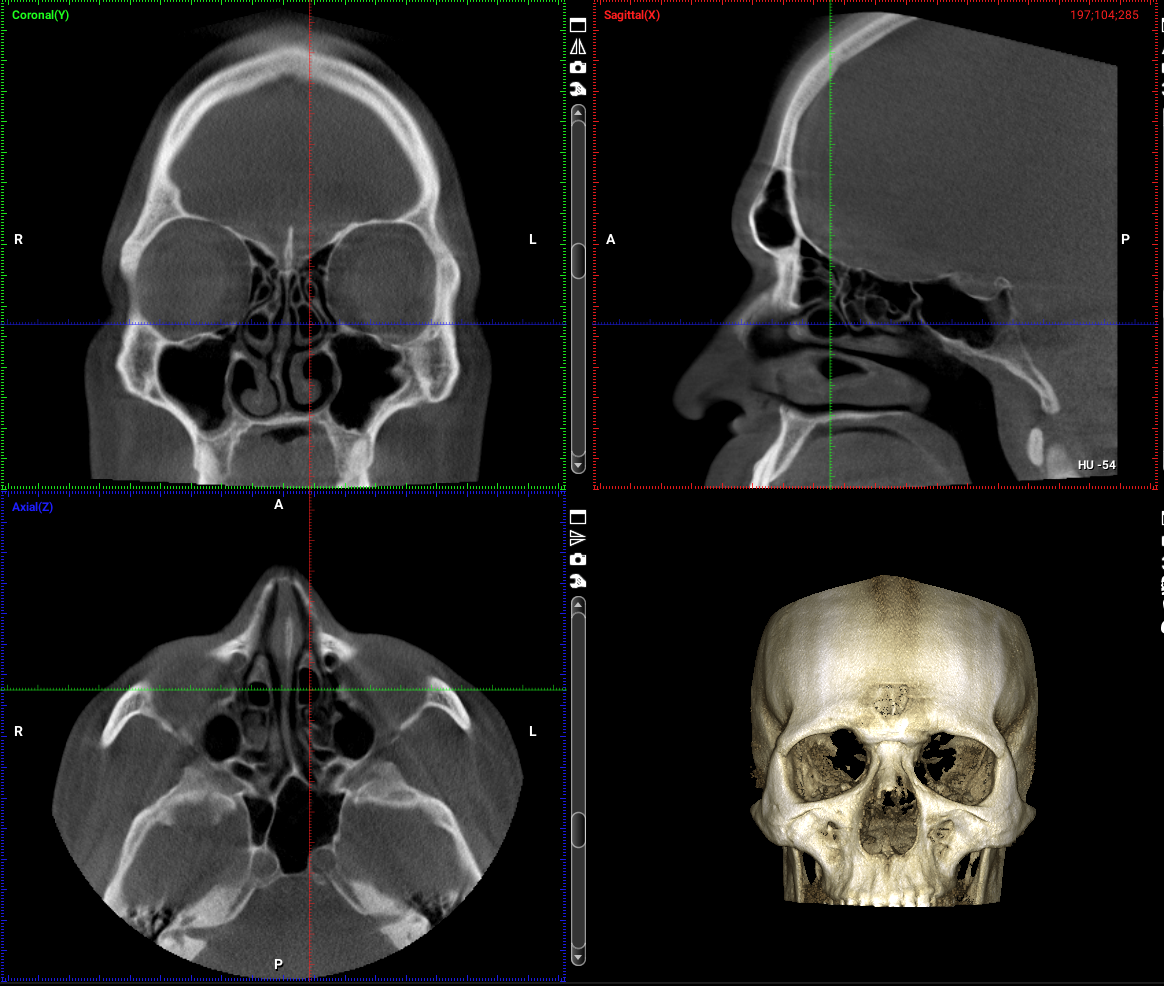

Neben der konservativen Behandlung sämtlicher HNO-Erkrankungen liegt ein besonderer Fokus unserer Einrichtung auf operativen Eingriffen, insbesondere in der minimalinvasiven Chirurgie bei Nasenatmungsstörungen, chronischen Nebenhöhlenentzündungen und Schnarchproblemen. Jährlich führen wir etwa 500 ambulante und stationäre Operationen durch.

Erkrankungen der Nase und Nasennebenhöhlen